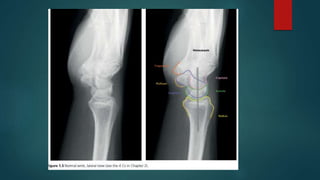

Skeletal X ray anatomy ,colour description, Imaging anatomy of musculoskeletal X rays, Diagnosis imaging anatomay, Radiology